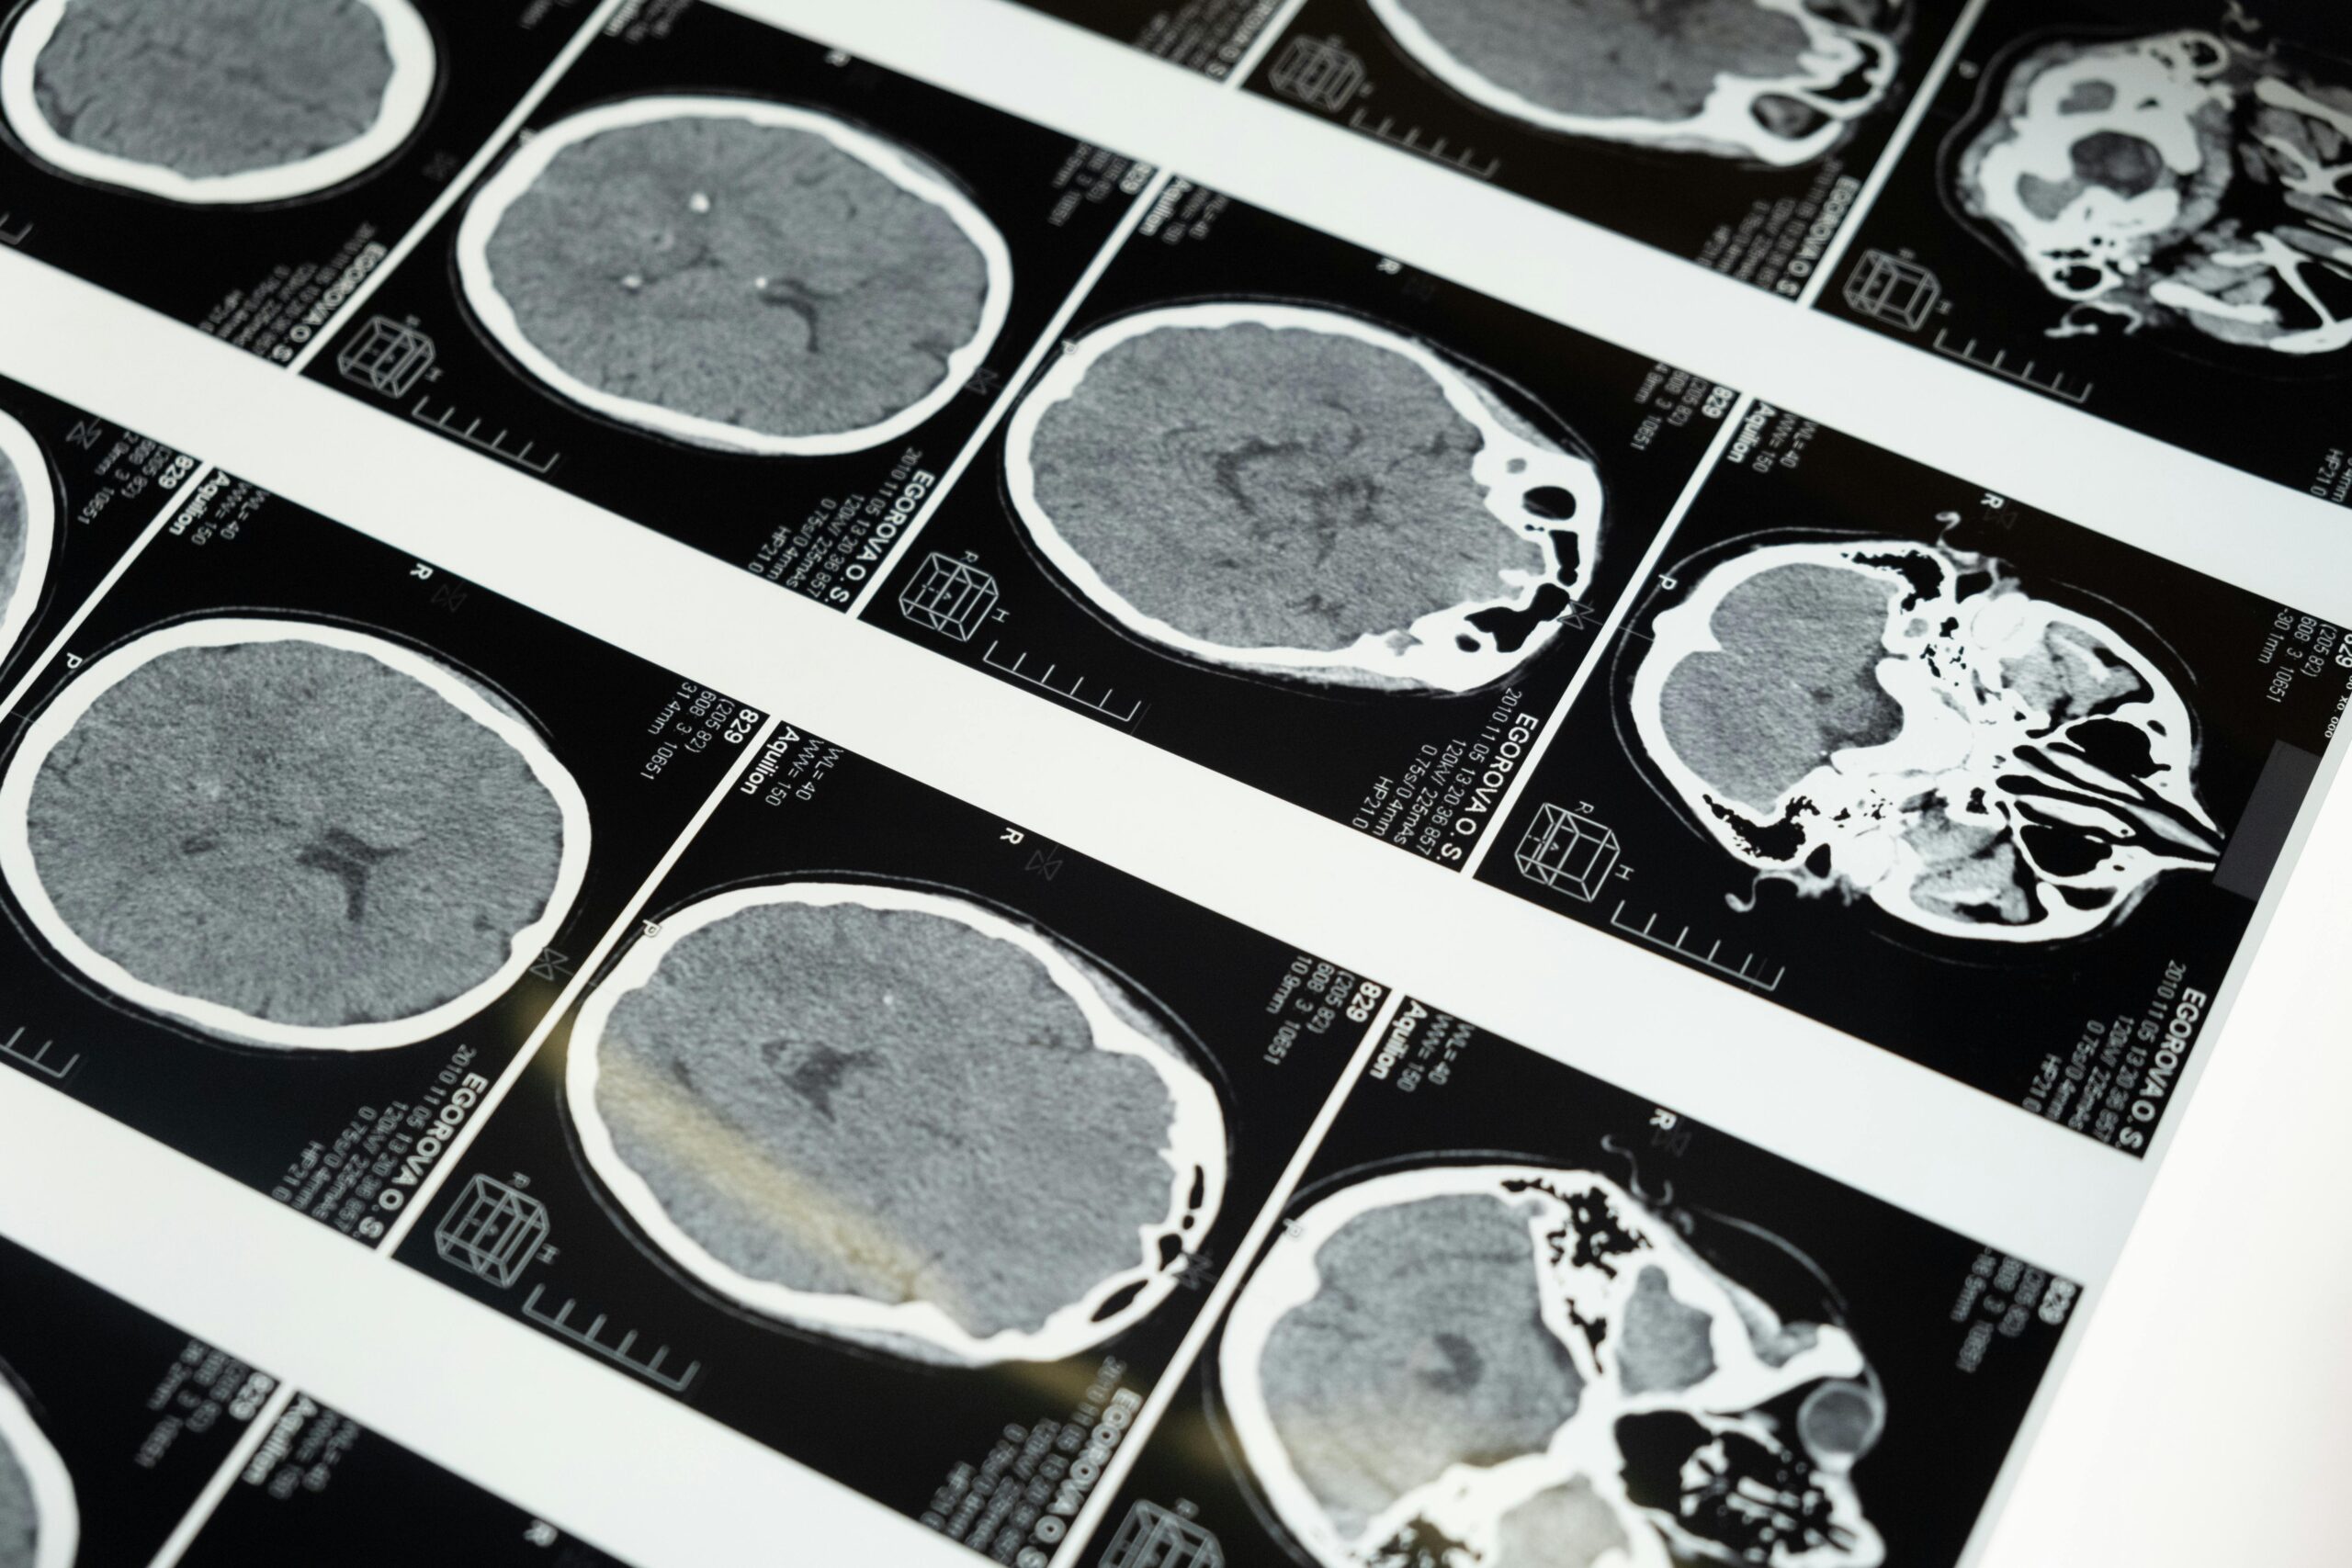

Descoberta recente da Universidade da Califórnia indica que pessoas com transtornos de ansiedade apresentam, em média, 8% menos colina no córtex pré-frontal.

Esse achado reflete a análise de 25 estudos anteriores, que reuniram dados de 712 participantes, dos quais 370 tinham diagnóstico de ansiedade. A redução desse nutriente, essencial para a função cerebral, pode abrir novas frentes no tratamento de distúrbios emocionais.

Níveis reduzidos de colina no cérebro, em particular no córtex pré-frontal, comprometem funções cognitivas essenciais. Essa ligação sugere que intervenções futuras podem aproveitar essa descoberta no desenvolvimento de tratamentos.